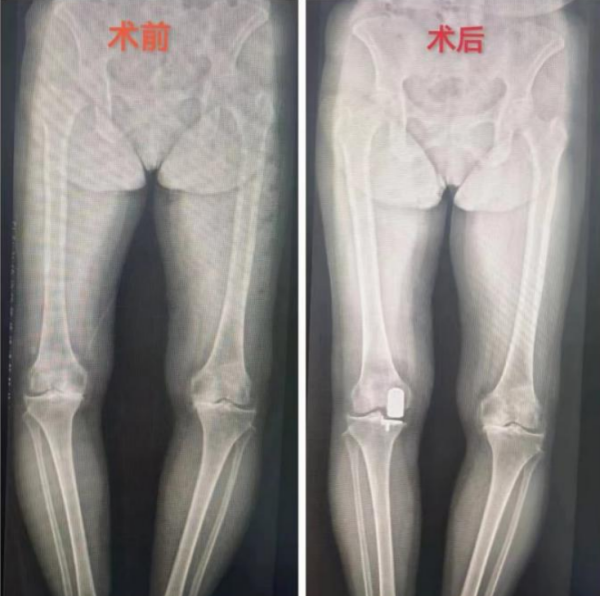

在临床案例展示部分,李良军深入讲解了来我院运动医学科住院手术的老人。65岁的刘奶奶(化名),五年前确诊膝关节退行性病变,但没有接受治疗。一个月前,她的右膝关节疼痛开始异常剧烈,尤其在上下楼梯、爬坡或下蹲时加重,且活动受限明显,已经到了无法忍受的程度。在家人的陪同下,她前往运动医学科就诊。李良军阅片后,诊断刘奶奶的膝关节主要是内侧软骨磨损的特点,决定为她施行内侧单髁置换术。

李良军解释,单髁置换术相比全膝关节置换术,保留了患者没有磨损的软骨和正常的韧带,只置换了膝关节内侧或者外侧间隙磨损的那部分软骨,所以手术创伤更小、患者恢复更快,术后行动更加自如。本次手术十分成功,术后第二天,刘奶奶在病房走廊上自信地练习行走,并热情地与旁边充满好奇的病友分享自己经历,劝大家一定要早诊断早治疗。